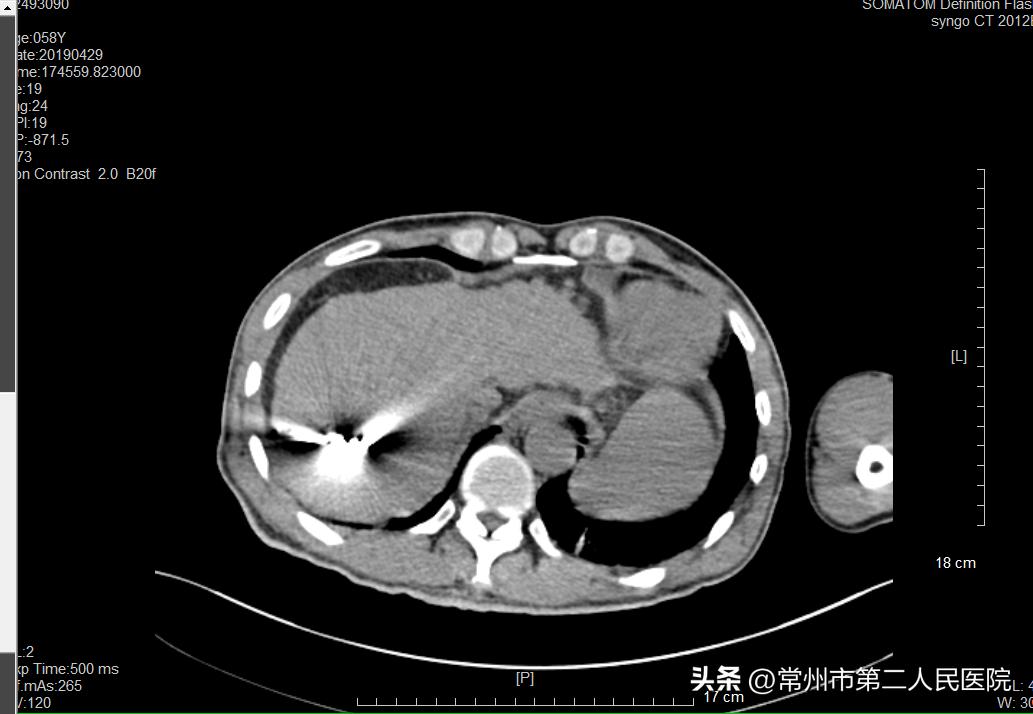

▲术中消融针穿刺到肿瘤处

“像姚先生这样的病例,过去治疗方法包括肝切除术、全身静脉化疗,现在介入治疗成为部分肝癌首选治疗方法。治疗过程中,我们将一根铅笔芯粗细的消融针,在CT引导下穿刺入肿瘤内,外接消融治疗仪,以90℃以上的温度直接将肿瘤组织碳化灭活。治疗5cm以内的原发性肺癌、原发性肝癌可达到与手术切除相当的治疗效果;对于肺、肝转移性癌进行部分或完全灭活可起到减轻患者肿瘤负荷、延长生存时间、提高生活质量的效果。由于治疗时间短,患者的损伤小,术后2-3天就可以出院恢复正常生活。”